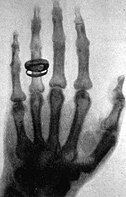

• Röntgen: los rayos X

Röntgen: los rayos X

Utilizando un tubo de Crookes, fue quien produjo en 1895 la primera radiación electromagnética en las longitudes de onda correspondientes a los actualmente llamados Rayos X.